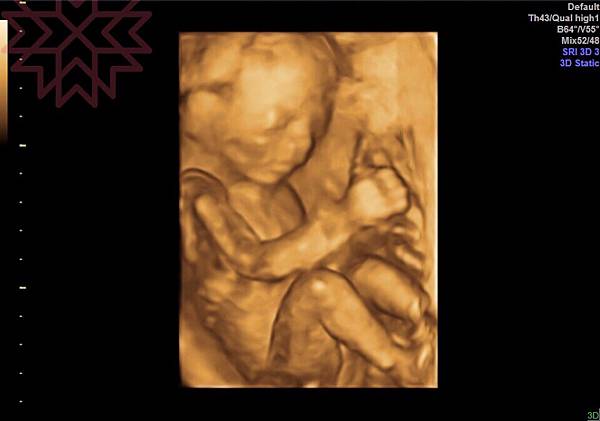

終於等到禮拜二的到來,其實還滿期待的,因為可以更準確的看到寶寶也可以確認他初步是否健康;雖然高層次不保證100%準確度,但照了還是可以讓媽媽們放心。安排的時間是晚上8點,報到後等了一下,看進去的媽媽都還滿快就結束的,想說寶寶應該也會乖乖的給照吧。輪到我的時候快接近8點半,一開始照的時候我想說都還滿順利的啊,血流、五臟六腑、四肢、有沒有兔唇等等的,五官正面照也很清晰,技術員也幫我存檔了影片,可以看到寶寶頑皮的在玩腳和吃手手。但技術員說寶寶因為趴著,所以心臟結構和手指頭擋住,所以要我起來走動一下,外頭的護理人員拿了一包巧克力請老公去泡給我喝,就這樣又等了20分鐘,換了個技術員進來,看看寶寶有沒有配合的往上轉;果然喝了甜的後,寶寶動得很大也終於成功的照到了剩下的心臟結構及5隻手指頭。我看光是單胞胎就花了那麼多時間,雙胞胎或更多胞胎的媽媽來照時,真的是考驗技術員的技術耶。技術員結束後,該黃醫師進來做最後的確認,除了前置胎盤的問題外,沒有什麼其他的問題,寶寶一切正常,所以黃醫師就說其他的到外面診間在解說。

一個多小時下來,也照了100多張,幫寶寶拍照確認健康也真的不容易啊。醫生又run了一次照片,確認寶寶性別和五臟六腑等,然後告知前置胎盤應該是確認要剖腹了,因為我是偏全面性的前置胎盤,但又有點邊緣,所以下刀時比較容易,比較不會有大出血的問題;這期間我必須注意是否有大量出血,有任何問題都可以回到禾馨,他們有24小時的急診及住院醫師(但當然還是希望安穩的到生,黃醫師有解釋贈不是所有有前置胎盤的媽媽的都會出血,所以不要太擔心,放輕鬆)。黃醫師看我因為最近空氣髒,戴著口罩鼻子還是嚴重過敏,所以建議可以吃點舒緩過敏對孕婦也安全的藥物,然後胃食道逆流的問題也繼續開藥給我,讓我比較好入眠。有順便詢問關於最近常常覺得要暈倒的問題,黃醫師說懷孕後的媽媽有部分會出現『姿勢性低血壓』的症狀,能解決的辦法就是放慢動作,提醒自己是個孕婦,要換姿勢時都慢慢的,讓血液慢慢的流回需要的地方,能夠紓緩症狀。要離開時都已經9點多了,辛苦黃醫師那麼晚還在診間。

附上我們家的小帥哥特寫